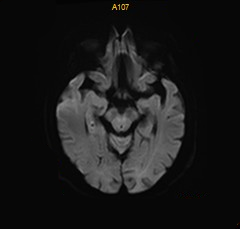

术前影像

1年前的MRA提示该部位重度狭窄。